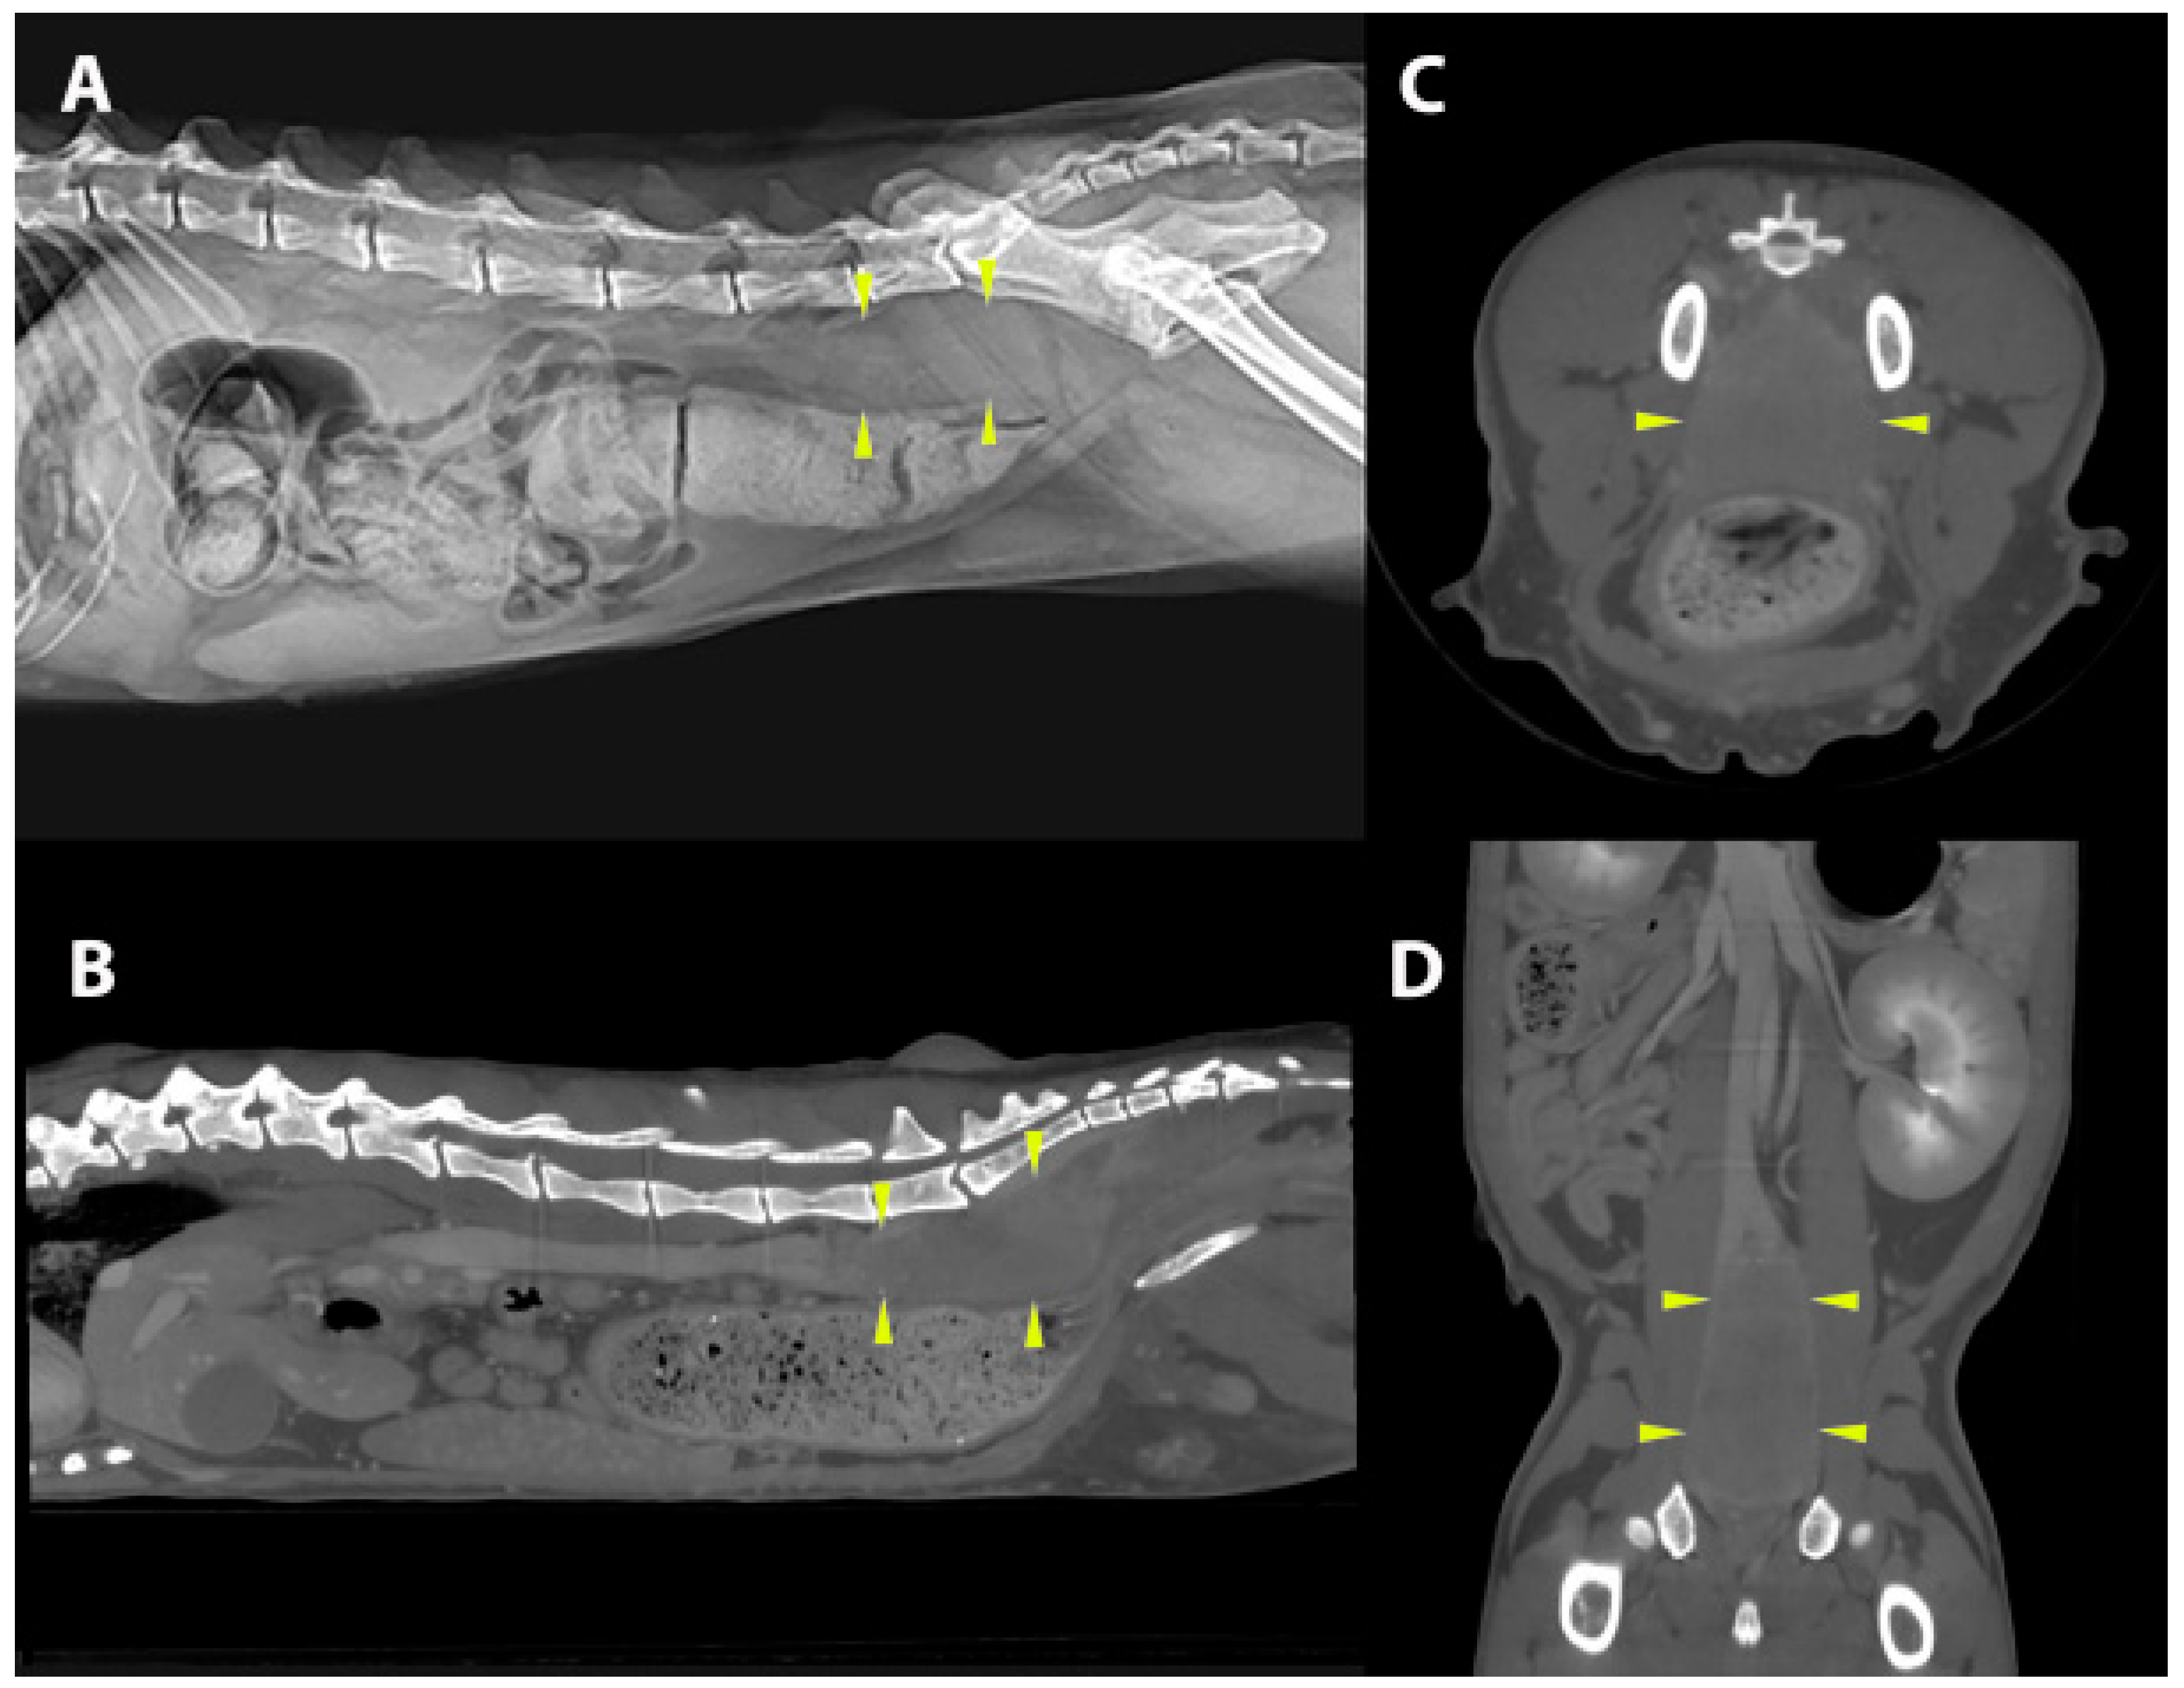

3.1.2. Extracutaneous Lesions

| 8 | Persian | 9 | MN | EC, S | Sub-lumbar mass | IB | −ve | ND | +ve | ND | ND |

| 20 | ESH | 7 | FN | EC, S | Intra-abdominal/vaginal | EB, IC | M. canis | M. canis | ND | +ve | ND |